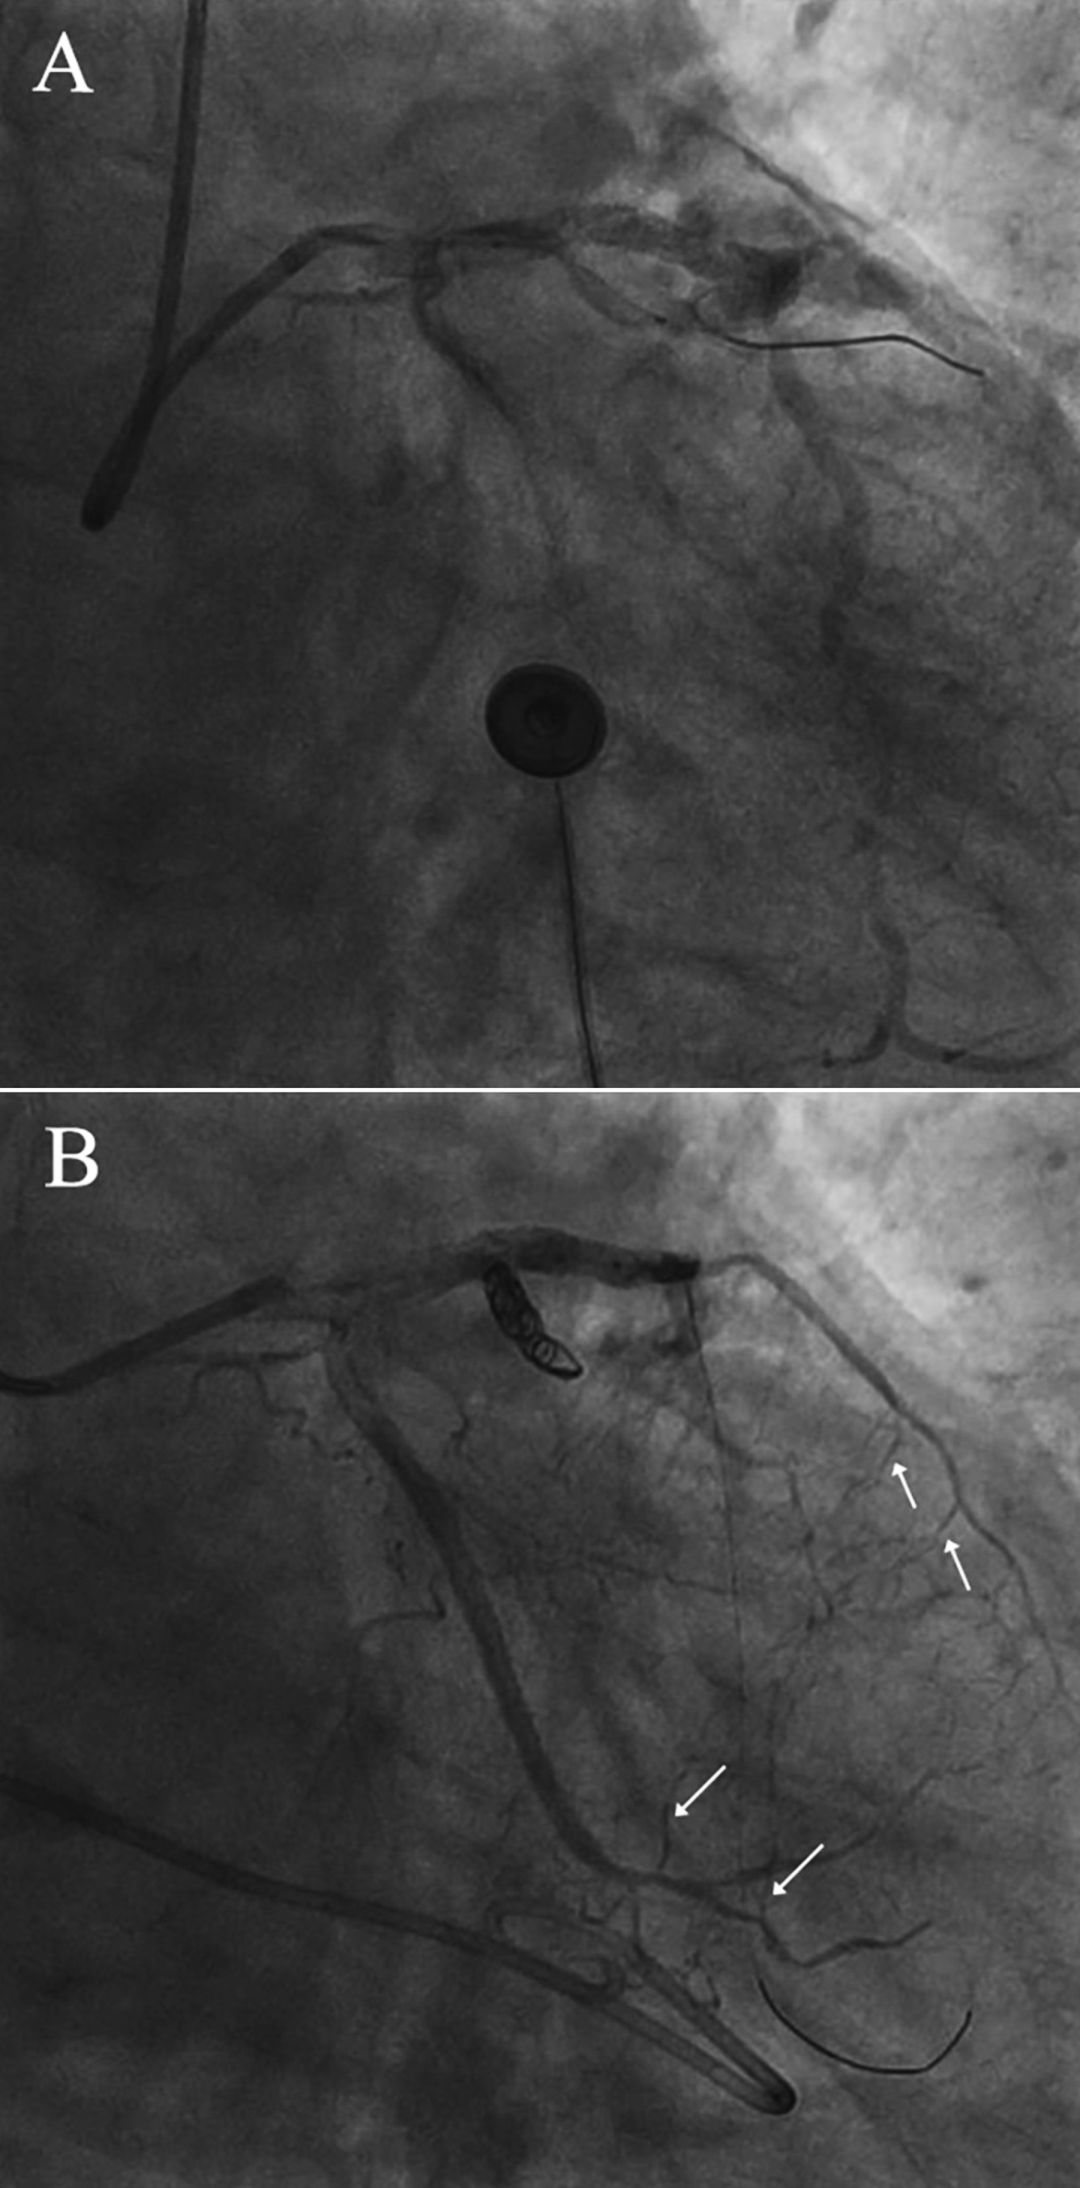

尝试近端弹簧圈封堵:远端侧支循环迅速开放(图3B)

图3冠状动脉破裂的确认及介入治疗

(A)明显造影剂外渗(B)破裂血管的弹簧圈栓塞。箭头指向侧支循环。

环状扭曲处穿孔后,远端迅速形成多支侧支循环(图3A)